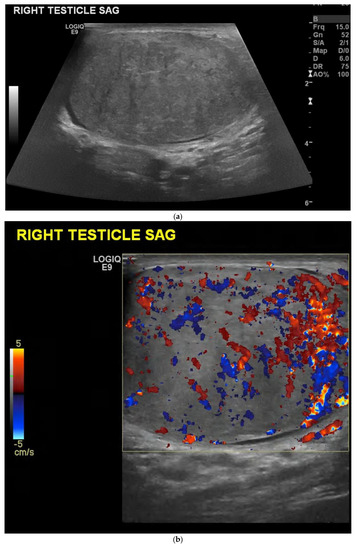

4.1. Seminomatous Germ Cell Tumour

| Seminomas | Homogenous and hypoechoic Well circumscribed Occasionally contain cystic components or calcifications |